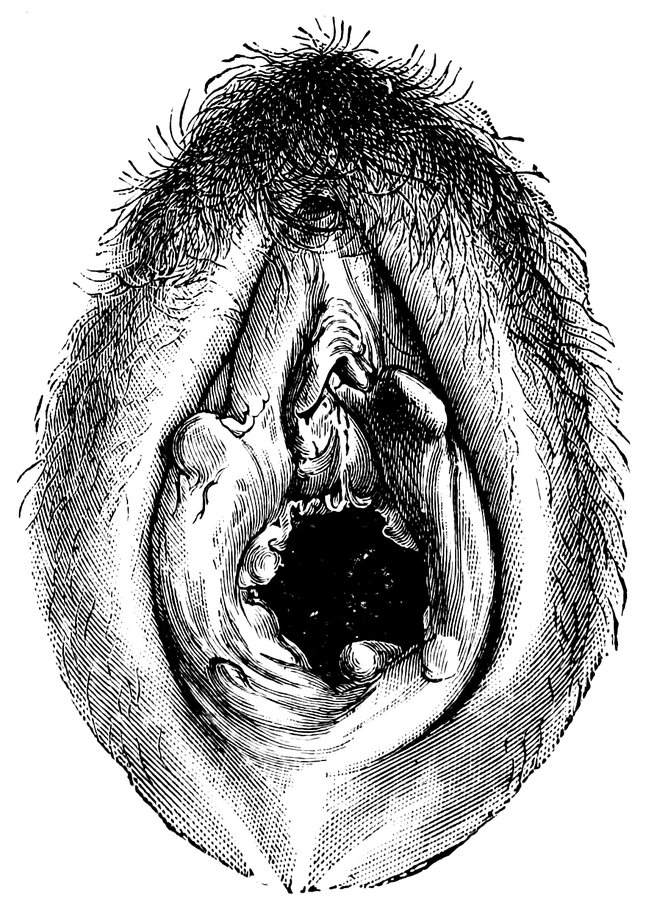

| 12. | Female external genital organs of a virgin | 54 |

| 13. | The external genital organs of a virgin | 55 |

| 48. | The female pudendum, or vulva, with the labia majora | 204 |

| 49. | Vestibule of the vagina, with the labia minora or nymphæ, etc | 205 |